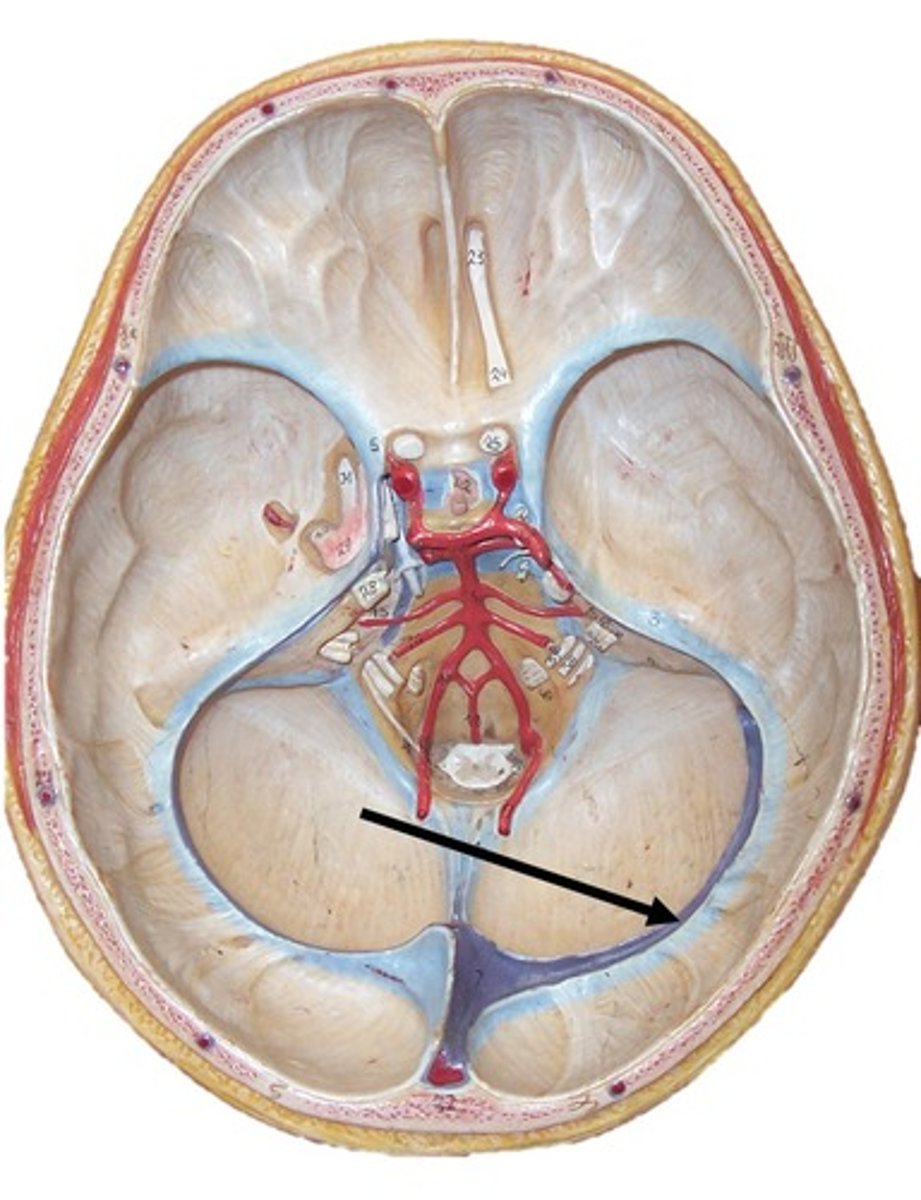

Dural reflections consist of what?

falx cerebri

tentorium cerebelli

falx cerebelli

separates the two cerebral hemispheres

Falx cerebri contains what sinuses?

superior and inferiorer sagittal sinuses

separates middle and posterior cranial fossae, covers upper surface of cerebellum

Outer border of Tentorium cerebelli contains what sinsus?

transverse sinus

separates cerebellar hemispheres

Falx cerebelli contains what sinus?

occipital sinus

What sinus is between the falx cerebri and tentorium cerebelli?

straight sinus

Confluence of sinuses

meeting place of the sinuses where they later go to the transverse sinus to the sigmoid sinus and out of the internal jugular vein